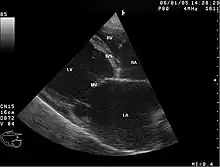

Abnormal heart sounds, murmurs, ECG abnormalities, and enlarged heart on chest x-ray may lead to the diagnosis. Echocardiogram abnormalities and cardiac catheterization or angiogram to rule out coronary artery blockages, along with a history of alcohol abuse can confirm the diagnosis.[4] It's important to note that part of diagnosing Chronic ACM is noting the absence of coronary artery disease.[7] It's also worth noting that the diagnosis of ACM is largley a diagnosis of exclusion.

The diagnosis of alcoholic cardiomyopathy is typically made based on a combination of the patient's medical history, physical examination, and diagnostic tests.[8] Firstly, the doctor will ask the patient about their alcohol consumption habits, as well as any symptoms they may have experienced, such as shortness of breath or swelling in the legs.[8] They may also perform a physical examination to check for signs of heart failure, such as an enlarged heart or fluid buildup in the lungs.[8]

In addition to the patient's medical history and physical exam, the diagnosis of alcoholic cardiomyopathy is often confirmed with various diagnostic tests.[8] One of the most common tests is an echocardiogram, which uses ultrasound waves to create images of the heart and can detect abnormalities in the heart's structure and function.[8] Other tests may include an electrocardiogram (ECG) to measure the heart's electrical activity, and blood tests to check for elevated levels of certain enzymes that may indicate heart damage.[8] If the diagnosis is confirmed, treatment typically involves stopping alcohol consumption and managing heart failure symptoms through medications, lifestyle changes, and in severe cases, heart transplantation.[8]